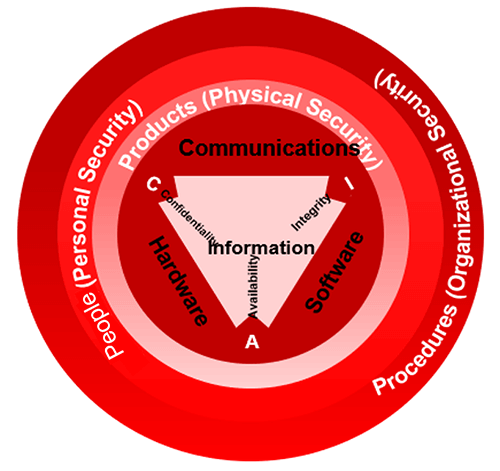

Security and Confidentiality

The NCCoE released a draft of the NIST Cybersecurity Practice Guide, SP 1800-24, Securing Picture Archiving and Communication System, on September 16, 2019. PACS is nearly ubiquitous in hospitals, prompting the Healthcare Sector to identify its security as a critical need. HDOs face many challenges in securing a PACS.

PACS requires controls that provide significant integrity, availability, and confidentiality assurances since it ties into doctor-patient workflow management. The results are based on image interpretation which aids in deciding a patient’s next step. These include the determination of health condition, follow-up visits, patient care, and other health-related actions. The three main tiers for possible confidentiality violations are Personnel servers, access points, and end-users.

Malware

PACS may have vulnerabilities that, given its central nature, may impact an institution’s ability to render patient care or to preserve patient privacy. These vulnerabilities could impede the timely diagnosis and treatment of patients if medical images are altered or misdirected. These vulnerabilities could also expose an institution to risks of significant data loss, malware and ransomware attacks, and unauthorized access to other parts of an institution enterprise network.

Confidentiality

Justice Samuel Dennis Warren and Justice Louis Brandeis define privacy as the right “to be let alone”. Information of a patient should be released to others only with the patient’s permission or allowed by law. When a patient is unable to do so because of age, mental incapacity the decisions about information sharing should be made by the legal representative or legal guardian of the patient. Information shared as a result of clinical interaction is considered confidential and must be protected.

The key to preserving confidentiality is to allow only authorized individuals to have access to information. This begins with authorizing users based on pre-established role-based privileges. The administrator identifies the user, determines the level of information be shared and assigns usernames and passwords. The user should be aware that they will be accountable for the use and misuse of the information they view and only have access to the information they need to carry out their responsibilities. Hence assigning user privileges is a major aspect of medical record security. Always remember HIPAA as you were taught in your radiography program.

Security Breach

Security breaches threaten patient privacy when confidential health information is made available to others without the individual’s consent or authorization. Keeping records secure is a challenge that doctors, public health officials, and federal regulators are just beginning to understand. Cloud storage, password protection, and encryption are all measures health care providers can take to make portable EHRs more secure.

Security Measures

Security measures such as firewalls, antivirus software, and intrusion detection software must be included to protect data integrity. Specific policies and procedures serve to maintain patient privacy and confidentiality. For example, employees must not share their ID with anyone, always log off when leaving a terminal and use their own ID to access patient digital records. A security officer must be designated by the organization to work with a team of health IT experts.